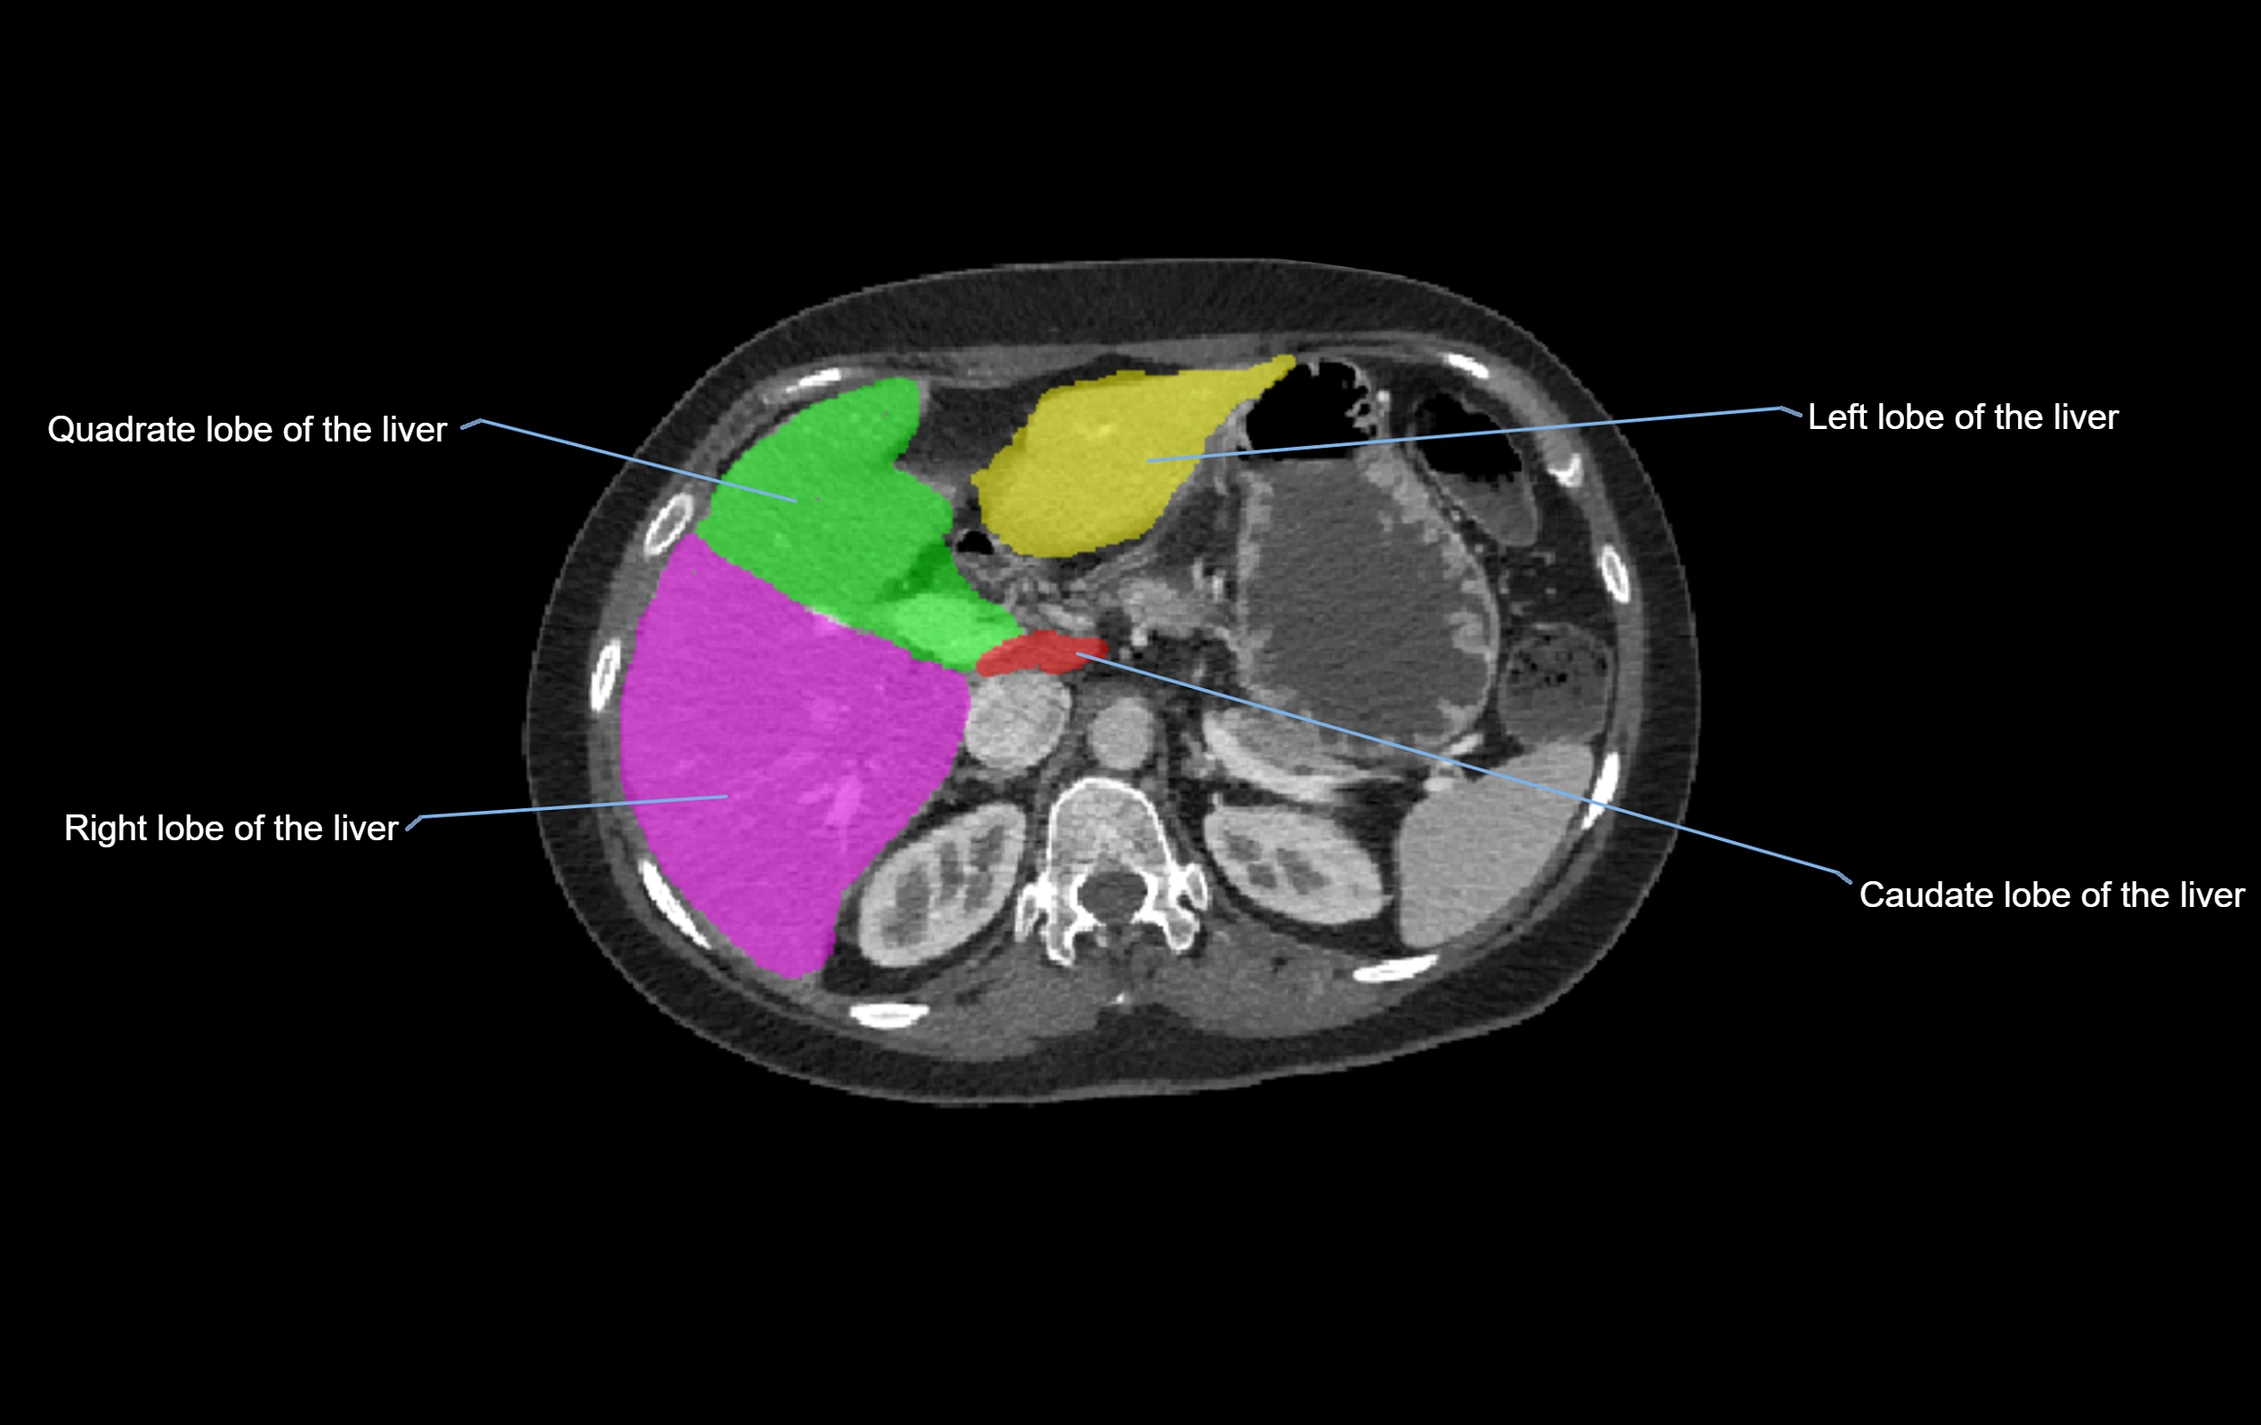

CT Image

image